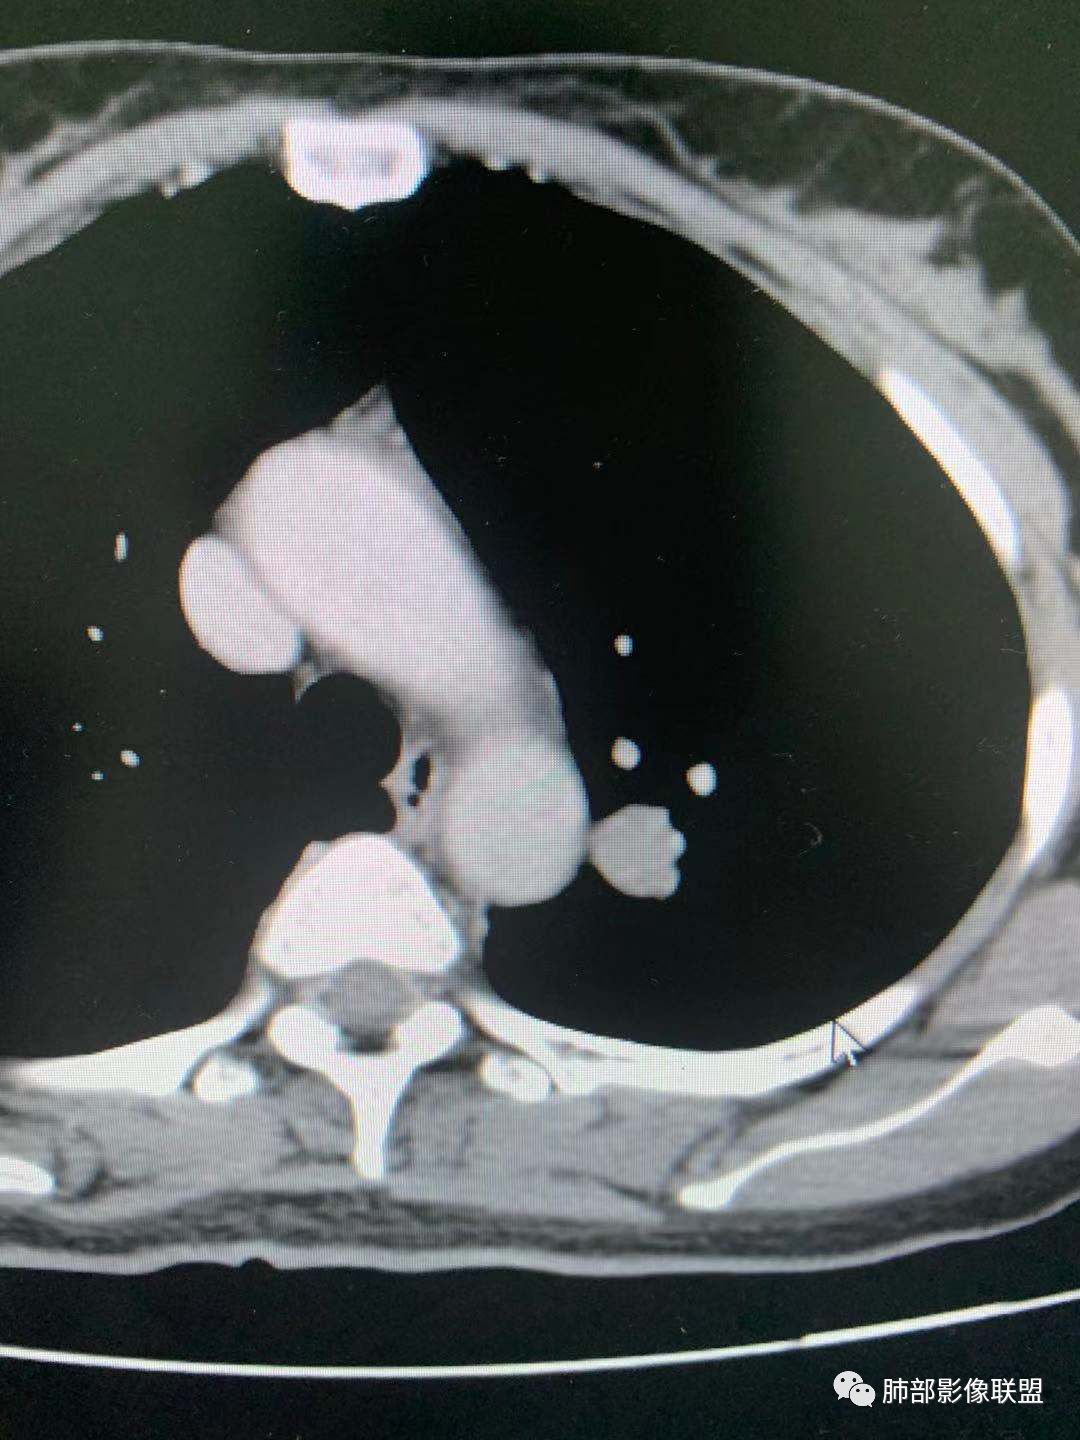

CT值30HU;增强后:41/76HU

强化幅度:46HU

边缘平直,延迟强化,血管贴边,支气管推移,毛刺较软,收缩力较弱。

一.尖后段高密度大结节:

1.左肺上叶尖后段较大类圆形实性密度结节影,密度均匀,中等程度强化。

2.实性密度区边缘相当清楚,表面欠光整,偶见毛刺、棘突和旁出血管结构,未见典型的深分叶及邻近胸膜凹陷。

3.可疑支气管进入受阻。可惜缺乏连贯图像或冠矢状位以资判断。

4.病灶与胸膜之间有连线,邻近段支气管及肺血管整体后移,提示病灶还是有一定收缩性。

如上,单就这实性结节,硬化性肺细胞瘤(PSP)和腺癌似乎都能够解释,形态太规整了一些。

5.病灶周围见边界清楚的磨玻璃影,有点醒目,有点意外!

这是无论如何不能忽视的征象!

这点强烈提示,要么整个病灶恶性(腺癌),要么良性病灶旁滋生恶性病灶。